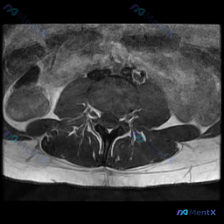

腰椎MRI轴位读片分享,这个椎间盘病变很典型你能看出来吗?

这是一份腰椎MRI T2序列轴位影像,层面位于下腰椎节段(L4/5或L5/S1,具体需结合矢状位确认)。

- 椎间盘改变:该节段椎间盘后缘形态不规则,有明显的后方局部突起,椎间盘组织向椎管内延伸,对椎管前缘形成占位效应;椎间盘内部是混合信号,髓核区域信号强度降低,提示椎间盘脱水退变。

- 神经结构受压:突出的椎间盘向后压迫硬膜囊,导致硬膜囊前缘明显受压凹陷变形,硬膜囊横截面积减小;双侧侧隐窝空间狭窄,存在神经根受压的可能性,从轴位看属于典型的后方中央型或旁中央型突出。

- 伴随退变征象:椎体后缘可见轻微骨质增生,后方关节突关节有轻度增生肥大,后方黄韧带没有明显肥厚,也没有看到明显的肿瘤或感染征象。